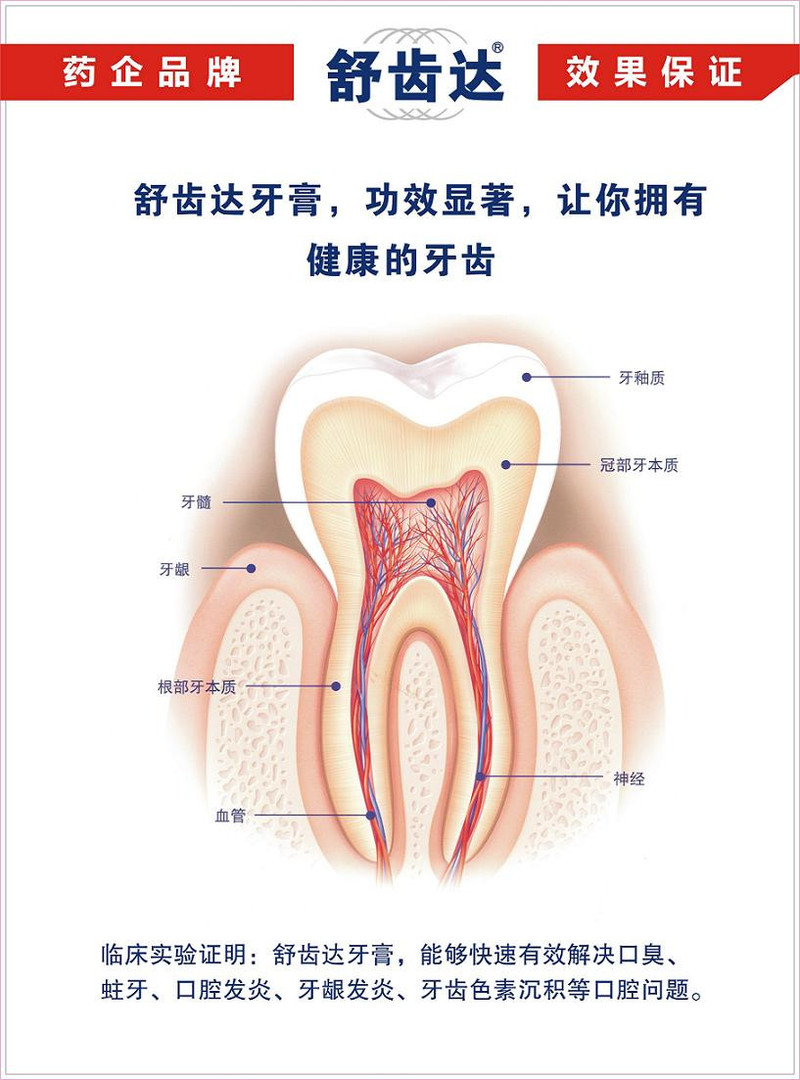

攻略:舒适达牙膏的作用和功效,选对了才能远离牙齿敏感!你是否也有过这样的经历:每次喝一口冰水或吃一块冷饮,牙齿就像被电击一样疼痛?或者在刷牙时,牙齿也会有刺痛感?如果你也有这些困扰,那么你可能是牙齿敏感的受害者。 作为一名长期遭受牙齿敏感困扰的人,我尝试过各种方法来缓解这种不适感。从改善刷牙习惯到尝试不同的牙膏,我...